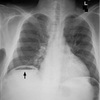

Dx

Neumotorax en pulmón derecho